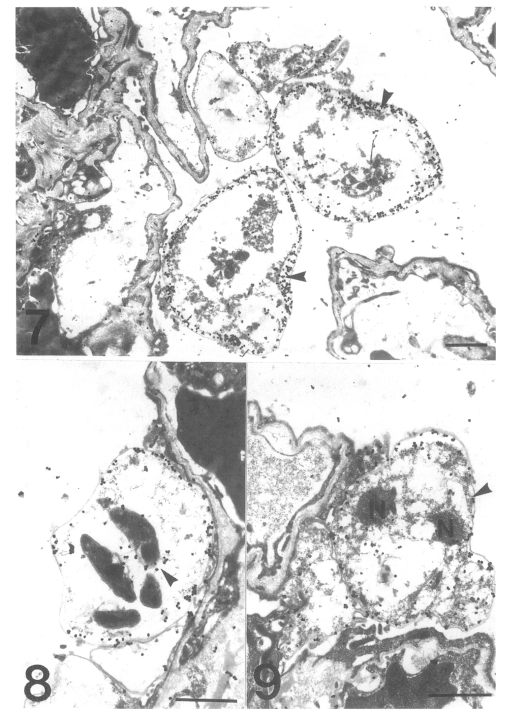

Localization of cytoskeletal proteins in Pneumocystis carinii by immuno-electron microscopy

The Korean Journal of Parasitology 2001;39(1):13-21.